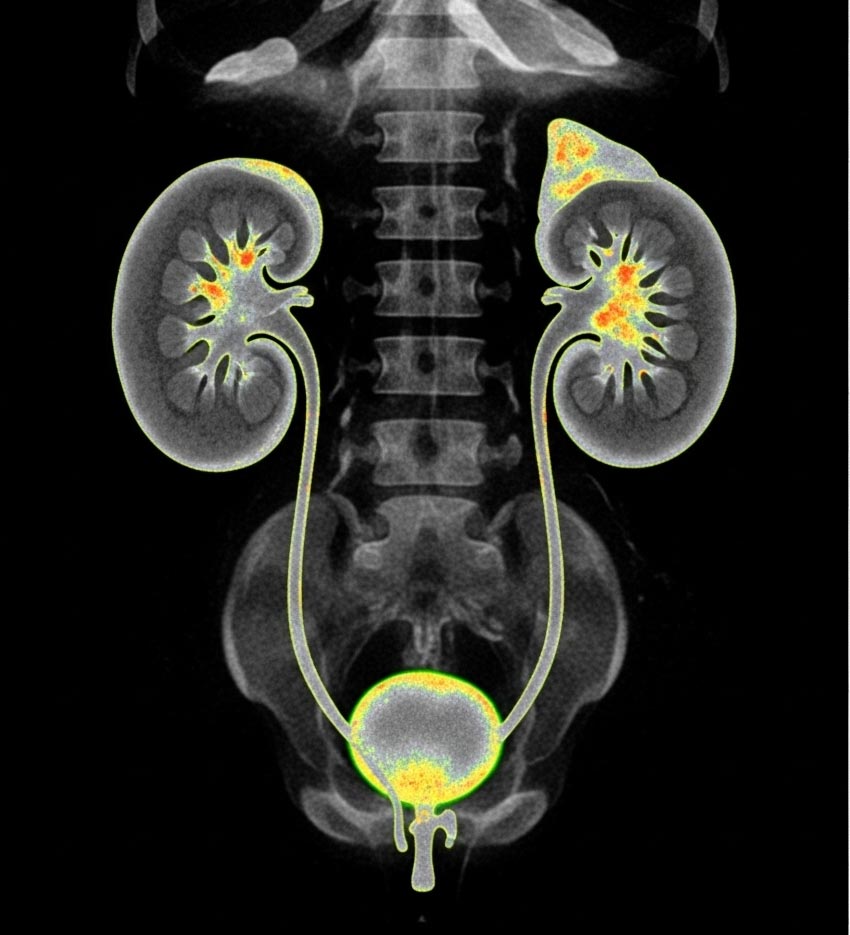

اسکن هسته‌ای کلیه یک روش تصویربرداری پزشکی است که با استفاده از مقدار بسیار کمی ماده رادیواکتیو، عملکرد واقعی کلیه‌ها را بررسی می‌کند. برخلاف سونوگرافی یا سی‌تی‌اسکن که بیشتر ساختار و شکل ظاهری کلیه را نشان می‌دهند، این روش بر ارزیابی عملکرد کلیه‌ها تمرکز دارد. در این اسکن مشخص می‌شود که کلیه‌ها چگونه خون را تصفیه می‌کنند، ادرار را با چه سرعتی تولید و دفع می‌کنند، آیا مسیر خروج ادرار دچار انسداد شده است یا خیر و به طور کلی کلیه‌ها تا چه اندازه وظایف طبیعی خود را به درستی انجام می‌دهند.

• این ماده وارد کلیه‌ها می‌شود و روند رسیدنش، جذبش و خروجش توسط دوربینی به نام «گاما کمرا» ثبت می‌شود.

۵. کنترل وضعیت کلیه پیوندی